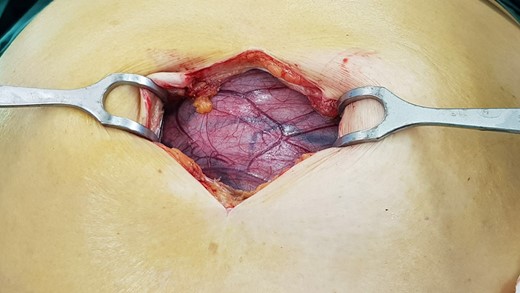

A laparotomy was performed to resect the cyst for diagnostic and therapeutic purposes (Figs 2 and 3). The cyst was noted to originate from the sigmoid mesocolon. No other viscera required resection. The patient made an uneventful recovery.